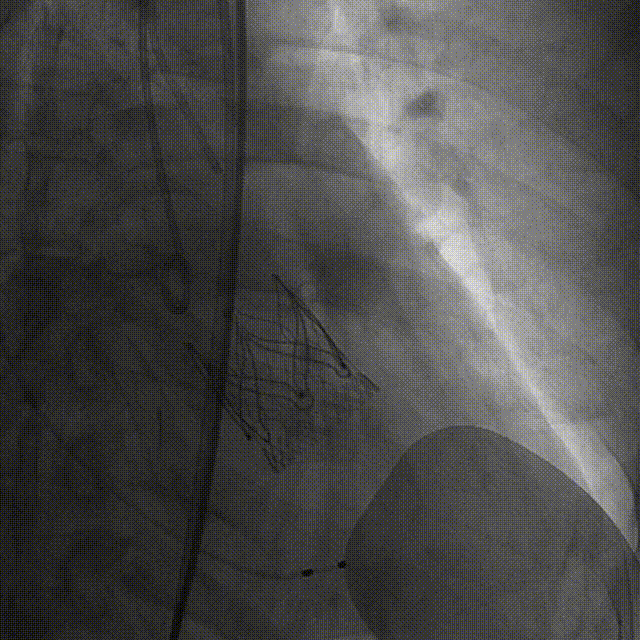

Case 4

重度反流心衰伴冠脉多支病变

(EF37%)

手术过程:5A 标准化流程SOP

术后造影